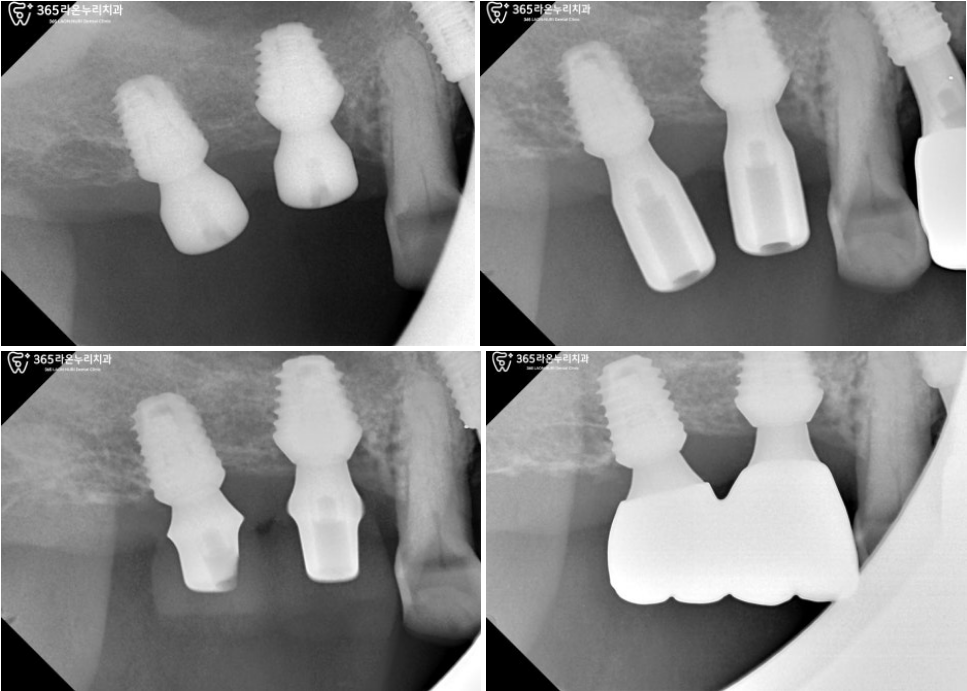

그렇게 유착되기를 기다리면서

오른쪽 위 아래 모두 어버트먼트+임시 치아를

올려드린 모습입니다.

그이후, 아래턱에 최종 크라운을

올려 튼튼한 치아를 완성했습니다.

시간이 흘러, 오른쪽 위턱의 어금니부위도

잘 완성되어 최종 크라운까지 올려드릴 수 있었습니다. ^^

▮ 3.최종 보철 장착

최종 크라운들이

흔들리거나 위태로운 곳 없이

잘 제작되었습니다.

치아색과 유사하게 제작되어

어색하지 않고 편안한 인상을

자아내고 있습니다.